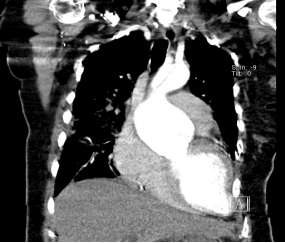

患者由于呼吸急促只能半卧位检查加上肺部气体干扰,升主动脉显示不清晰,在多切面仔细扫查下陈泉医师在高位胸骨旁切面发现主动脉内有一个隔膜样的结构,初步怀疑患者有主动脉夹层可能。

▲床旁心超主动脉发现异常隔膜(箭头所指)

但患者发病后并未有明显的胸痛表现,家属自诉患者产前曾在外院心超检查就曾发现主动脉内有异常的分隔,主动脉瓣有轻度反流。但由于产妇没有明显症状,故没有进一步治疗直至产后。

尽管患者临床症状和病史不太支持夹层,但根据多年的工作经验陈泉医生还是坚持给出了主动脉夹层的诊断,并且考虑是夹层累及了主动脉瓣,从而导致主动脉瓣反流的加剧。

超声具有便携性好、普及率高等优势,可用于主动脉夹层的初步检查。其诊断主动脉夹层的主要征象为发现主动脉内随心动周期摆动的隔膜回声,并可同时评估患者的心功能、主动脉瓣情况。但经胸超声穿透力低,易受肺部气体干扰,超声并不一定都能发现主动脉内撕脱的内膜,因此对于有主动脉夹层高危因素且超声提示主动脉瘤样扩张的病人即使临床症状不典型,也因考虑到此病并行CTA检查进一步明确诊断。